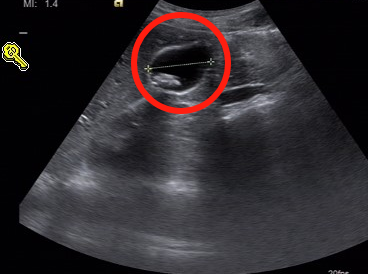

肝胆外科许明友主任医师接诊后,初步了解到小张的情况,为其安排了B超和CT等检查,经过一系列检查后发现患者被确诊为胆囊结石伴胆囊炎。

许主任表示:“小张的情况,需要进行腹腔镜下胆囊切开取石术,因为这个手术是微创手术,不仅能够保住患者的胆囊,还能精准地取出胆囊里的石头。”

在完善相关术前准备后,小张同学被推进了手术室。术中,许主任在腹腔镜和胆道镜的引导下,准确定位到胆囊。

在保证胆囊功能正常,不切除患者胆囊的同时,取出胆囊结石。